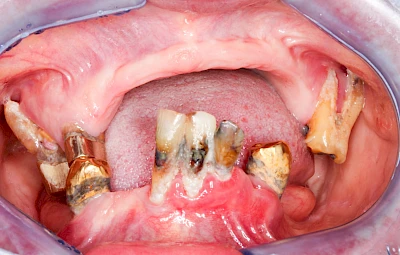

Gingivitis & Parodontitis: Stadien

Ist zunächst nur das Zahnfleisch von der Entzündung betroffen, spricht man von Gingivitis. Später, wenn auch der Knochen um die Zähne herum entzündet ist, spricht man von einer Parodontitis. Bei der Parodontitis wird der Knochen nach und nach abgebaut und das Zahnfleisch zieht sich zurück. Die Zahnhälse und Zahnwurzeloberflächen liegen mehr und mehr frei. Die Zähne werden zunehmend lockerer und fallen schließlich aus.